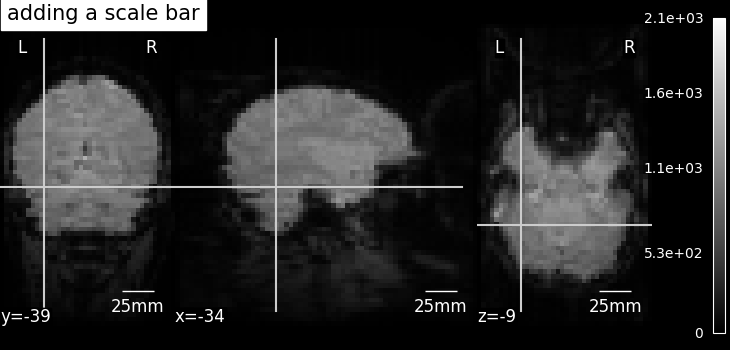

plot_scalebar

display.annotate(scalebar=True)

Adds annotations such as a scale bar, or the cross of the cut coordinates

Example: More plotting tools from nilearn